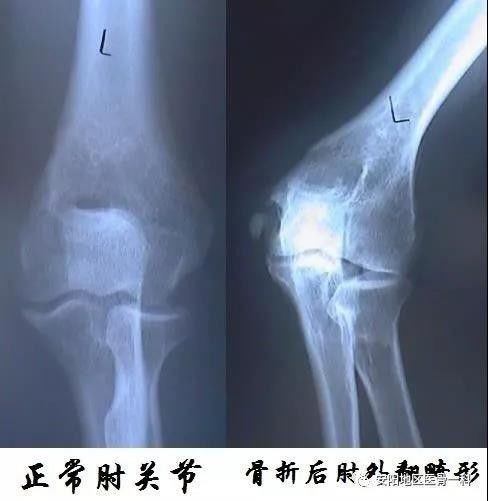

如果孩子骨折后出现肘内翻或肘外翻 需不需要治疗 小儿骨折 治疗方法 症状

肘外翻畸形怎么矫正 肱骨骨折 症状 治疗方法

儿童肘部损伤引起肘内翻畸形简介 佛山市中医院